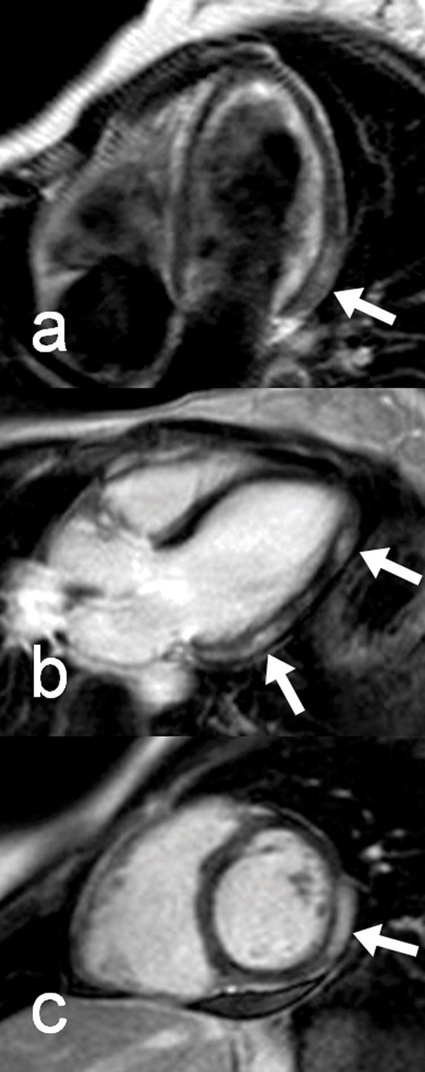

Entzündliche Myokardkrankheiten: Eine Domäne der Cardio-MRT ist die Myokarditis. War die akute Myokarditis aufgrund der unspezifischen Befunde bislang eher eine Ausschlussdiagnose, kann sie heute mit der Cardio-MRT direkt nachgewiesen werden. Typische Befunde sind Myokardödem und spezielle Muster der Kontratsmittelanreicherung (Abb. 2). Die chronische oder abgelaufene Myokarditis kann oftmals in Angrenzung zu ischämischen Myokardveränderungen als Ursache für eine eingeschränkte Ventrikelfunktion identifiziert werden. Andere Myokarderkrankungen können ebenfalls diagnostiziert werden. So spielt die Frage nach kardialer Beteiligung bei Systemerkrankungen eine immer wichtigere Rolle. Zu nennen sind dazu in erster Linie die Sarkoidose, aber auch Amyloidose, Sklerodermie und viele andere. Viele dieser Erkrankungen können mittels MRT mit hoher diagnostischer Genauigkeit identifiziert werden. Oft kann die Cardio-MRT deswegen den Patienten heute die Myokardbiopsie ersparen.